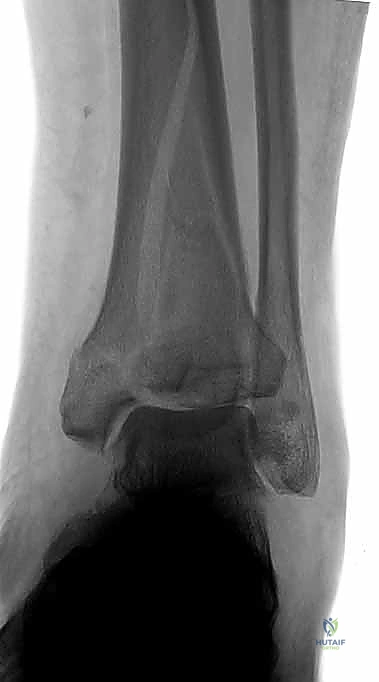

1. التصوير بالأشعة السينية التقليدية (X-Rays)

يتم أخذ صور من ثلاث زوايا (أمامية خلفية AP، جانبية Lateral، ومورتيس Mortise). تعطي هذه الصور فكرة عامة عن نمط الكسر، قصر الساق، ومدى انزياح العظام.